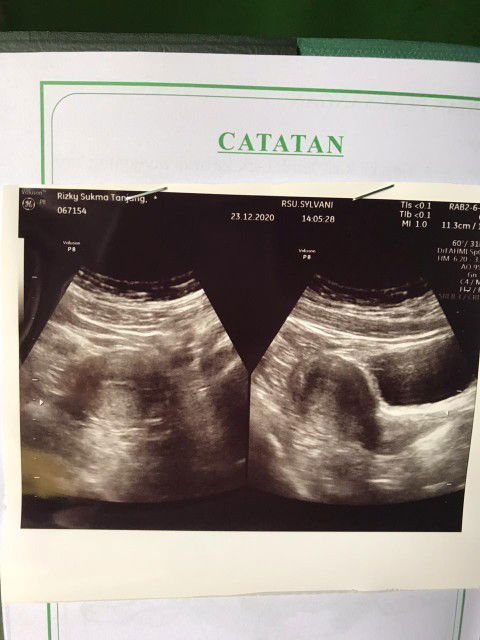

Kemarin aku usg, terus hasil usg mengatakan kantung janin ku gepeng, kemarin sama hari ini aku pendarahan. Tpi dokter gk langsung nyuruh gugurin. Dia blg "kita observasi dlu ya buk, tunggu 2 minggu sambil di kasih penguat janin". Ada ngak yang ngalamin kayak aku tapi janinnya berkembang sehat hingga lahiran😓#seriusnanya #bantusharing #jangandibully #firstbaby #Nanya